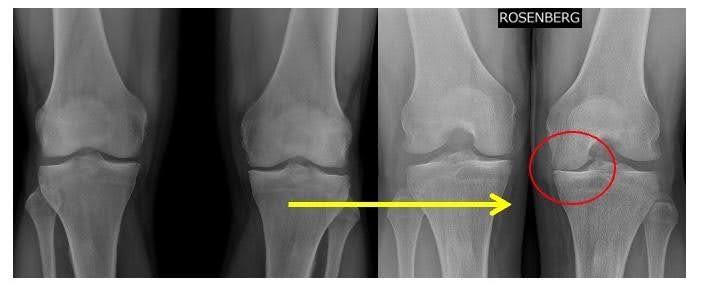

L’immagine mostra due tipi di radiografie:

- A sinistra: radiografia in carico standard (AP), dove l’artrosi può sembrare moderata.

- A destra: proiezione Rosenberg, che evidenzia meglio il restringimento dello spazio articolare, rendendo più chiara la gravità della patologia.

Questo esempio dimostra che un esame più specifico può cambiare l’approccio terapeutico, evidenziando un’indicazione più precisa per un intervento come la protesi monocompartimentale.